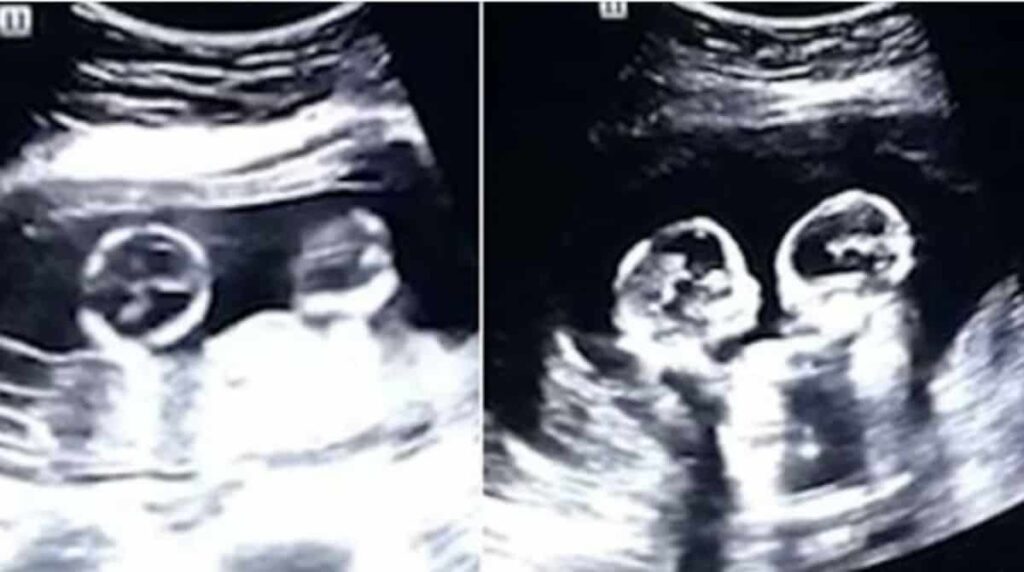

É rotina para muitas famílias aguentar e lidar com as típicas brigas entre irmãos, sejam gêmeos ou não. Por conta da familiaridade com o tema que atinge tanta gente, uma imagem de ultrassom mostrando duas gêmeas idênticas “brigando” ainda no útero, viralizou nas redes.

Uma das meninas parece empurrar a outra nas imagens do ultrassom. A cena divertiu o pai das pequenas. Tao, decidiu filmá-las e compartilhá-las nas redes sociais.

Depois o sucesso do vídeo, o pai das nenês fez questão de ressaltar que outros exames de ultrassom haviam mostrado as meninas abraçadas. “Nós achamos tão lindo ver as duas abraçadas! Eu acho que elas vão se dar muito bem! Mas também foi engraçado ver elas brigando”, conta Tao em entrevista ao jornal The Paper.